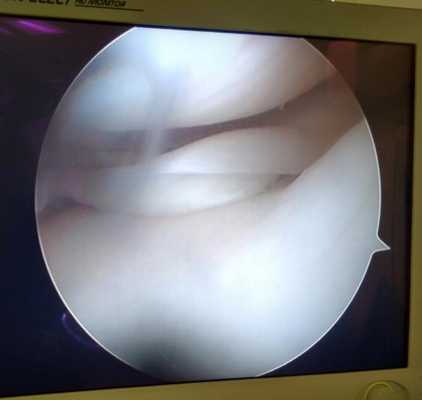

Изменения суставного хряща коленного сустава.

Суставной хрящ - гладкая, упругая и прочная соединительная ткань покрывающая кости образующие сустав. Это позволяет костям свободно скользить друг относительно друга в суставном соединении. В случае травм, повышенного износа, некоторых метаболических расстройств хрящ может изнашиваться, вызывая боль и ограничение объёма движений. Артроскопия не лечит артрит или артроз, но может снизить болевой синдром и позволить частично восстановить хрящевое покрытие костей в суставе за счёт таких вмешательств как хондропластика, дебридмент и микрофрактуринг и ряд других.

Продольные трещины на хряще большеберцовой кости после эпизода подкашивания после разрыва передней крестообразной связки коленного сустава.

Дегенеративные изменения суставного хряща коленного сустава появляющиеся на фоне повреждения разорванным мениском.